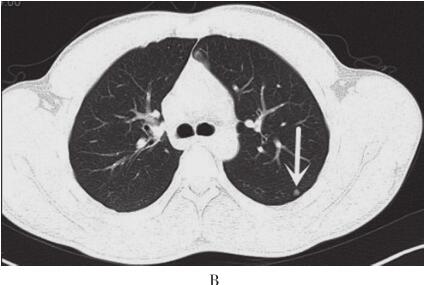

图2 2012年11月15日胸部CT平扫+强化

A.右肺中叶内侧段可见大小约5.7cm×5.0cm软组织肿块,有浅分叶,边缘清晰;B、C.双肺可见多发大小不等结节灶;D.肿块增强扫描呈中度强化